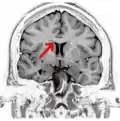

-

Coronal T2 (grey scale inverted) MRI of the brain at the level of the caudate nuclei emphasizing corpus callosum - Tractography of corpus callosum